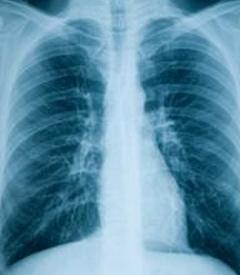

Отек легких — это состояние здоровья, при котором у пациента избыток жидкости в легких затрудняет дыхание. В некоторых случаях проблема может быть опасной для жизни, особенно когда накопление жидкости происходит внезапно. Воздушные мешочки, называемые альвеолами, обрабатывают газы, поступающие в легкие, посылая кислород в кровь и удаляя углекислый газ через рот и носовые проходы. Когда у человека отек легких, воздушные мешки отягощаются жидкостью.

Возможные причины избытка жидкости в воздушных мешках многочисленны, но их можно разделить на две основные категории:

- Сердечный — левый желудочек не может перекачивать достаточное количество крови, возвращая ее обратно в легкие, или правый желудочек не может справиться с давлением легочной артерии.

- Несердечные — состояния, не связанные с работой сердца, могут вызывать накопление жидкости в воздушных мешках.